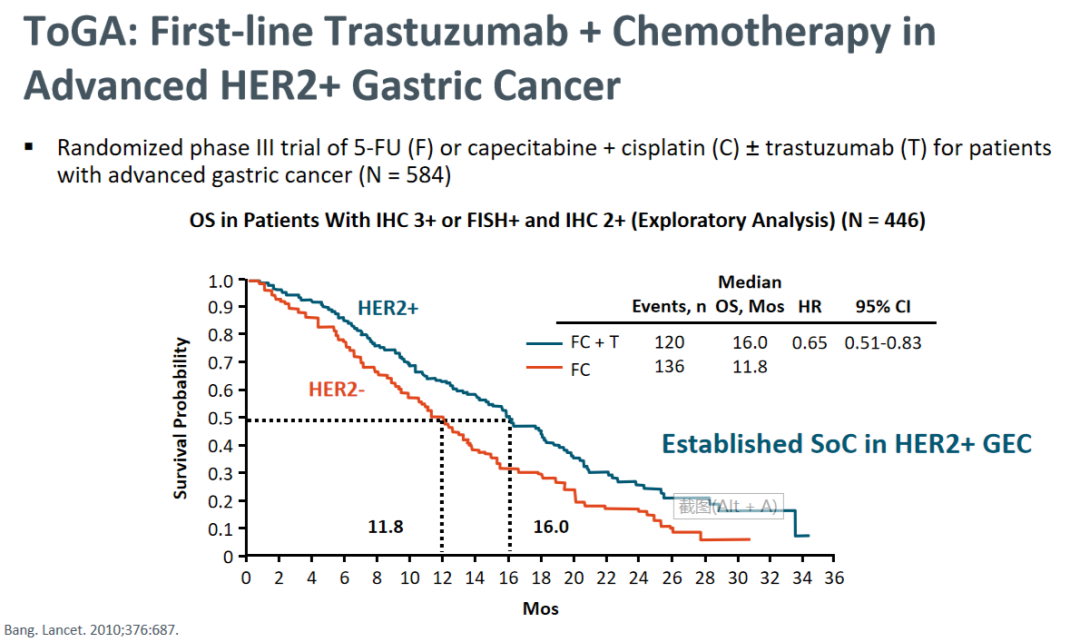

晚期胃癌的自然生存期是6-8个月,而化疗药物的应用将晚期胃癌的生存时间提高到10-12个月,2010年TOGA研究显示,与标准化疗(顺铂+氟尿嘧啶)相比,曲妥珠单抗联合化疗可使总生存期显著延长(11.8个月vs 16个月,P=0.0046),将胃癌常规化疗引导向胃癌靶向治疗时代,也奠定了曲妥珠单抗在HER2阳性胃癌一线治疗中的地位。继而在术后辅助治疗应用HER2靶向治疗且预后较好,PFS达到18个月,OS达到23个月,但这仍属于探索性研究,期待有更高级别的前瞻性研究得出结论。

TOGA研究:晚期HER2+胃癌一线曲妥珠单抗+化疗中位OS结果